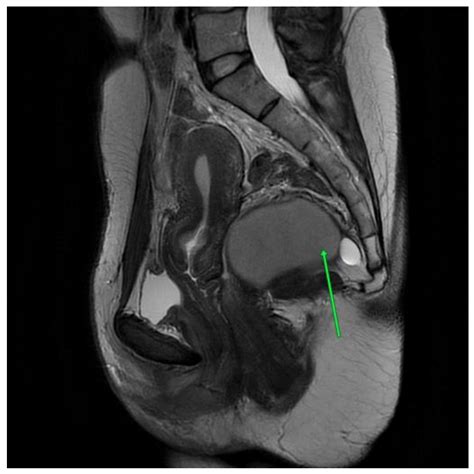

Diagnosing a cyst on the tailbone typically involves a physical examination by a healthcare professional. The doctor will examine the affected area and may order imaging tests, such as an X-ray or MRI, to rule out other conditions. In some cases, a sample of the cyst's contents may be taken for laboratory analysis to determine the presence of infection.